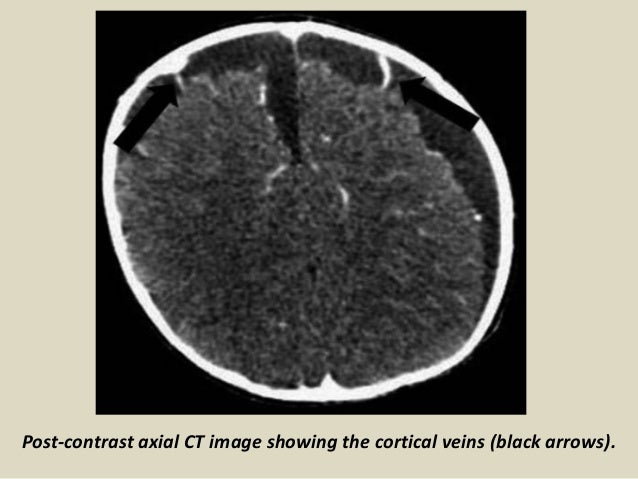

Radiology Signs

www.slideshare.net